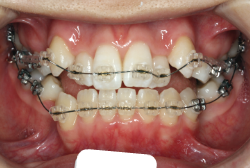

歯科矯正用アンカースクリューを用いた症例(骨格性反対咬合 非抜歯治療)

「ものがうまく噛めない」という主訴で来院したケースです。診断の結果、「骨格性反対咬合に伴う咬合不良+軽度叢生」と判明しました。原因としては特に下顎の左側が過成長したため、骨格性反対咬合になり、特に左側での噛み合わせが非常に悪くなっていると診断しました。初診時の写真を見ると、上下の正中線の大きなズレ、左側の噛み合わせの不良がはっきり分かります(黄色の矢印と緑の矢印は一致しているのが正しい状態です)。

そもそも、このような状態となっているのは骨の大きさに問題があるため生じていますので、場合によっては、「外科矯正」によって下顎の骨を外科的に縮めることで修正します。患者様が外科矯正をご希望されない場合は、従来ですと上下左右の小臼歯抜歯を行い矯正するのが普通です。

今回の患者様の場合は、「外科」も「小臼歯抜歯」も拒否されましたので、歯科矯正用アンカースクリュー(以下 アンカースクリュー)を用いて、下顎の歯列全体を後方に下げるという方法を取りました。

治療中の写真で、アンカースクリューより歯を後ろへ牽引しているのがお分かりいただけるかと思います。牽引を1年ほど続け、途中補助的に上下にゴムをかける(これを顎間ゴムと言います)手法なども追加し、全体で21ヶ月で治療を終えることが出来ました。

結局歯の本数を減らすことなく、すべてご自分の歯を残して、正しい配列と噛み合わせにすることができました。凸凹があまりひどくないため、簡単そうに見えると思いますが、このケースの初診の状態を見ると、熟練の矯正歯科医でも悩みのつきないケースです。まして、外科も出来ない、抜歯もイヤ、と言うことになると、従来の方法では治療不可能と考えられるのですが、アンカースクリューを使うことで最近は不可能が可能となってきました。